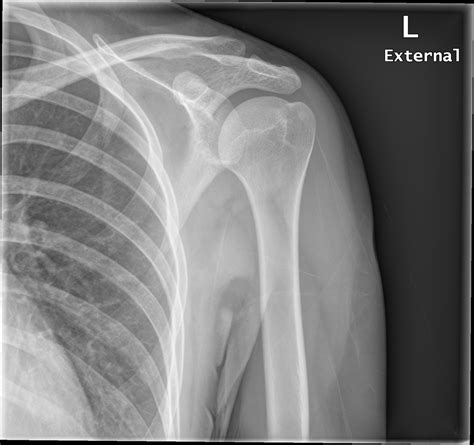

Understanding the intricacies of the X Ray Shoulder Joint is crucial for both medical professionals and patients alike. The shoulder joint is one of the most complex and mobile joints in the human body, making it susceptible to a variety of injuries and conditions. An X-ray of the shoulder joint provides valuable insights into the structure and health of this critical area, aiding in accurate diagnosis and effective treatment.

The shoulder joint is a ball-and-socket joint composed of three main bones: the humerus (upper arm bone), the scapula (shoulder blade), and the clavicle (collarbone). The joint is stabilized by a network of muscles, tendons, and ligaments, which allow for a wide range of motion. Understanding the anatomy is essential for interpreting X Ray Shoulder Joint images accurately.

Interpreting X Ray Shoulder Joint Results

Interpreting X Ray Shoulder Joint results requires a trained eye. Radiologists look for specific signs and abnormalities that indicate various conditions. Some key points to consider include:

• Bone Density: Changes in bone density can indicate conditions like osteoporosis or bone tumors.

• Fractures: Visible breaks or cracks in the bones.

• Joint Space: The space between the bones can indicate the presence of arthritis or other degenerative conditions.

• Soft Tissue: Although X-rays primarily show bones, they can also reveal certain soft tissue abnormalities.

Radiologists use these findings to make a diagnosis and recommend appropriate treatment options.